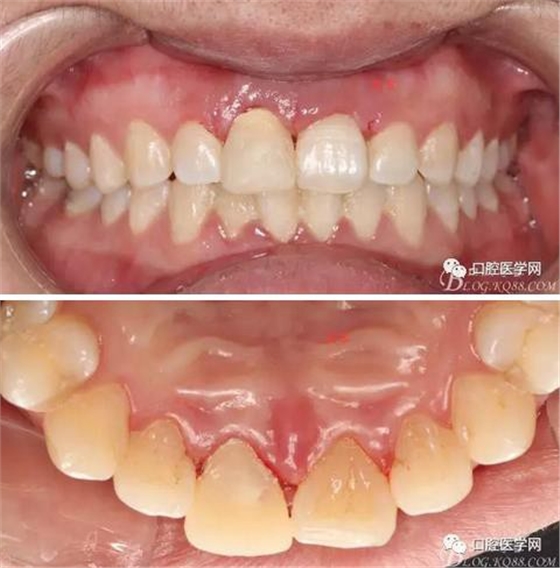

術(shù)后一周拆線

牙冠延長(zhǎng)術(shù)后6周復(fù)診牙齦齦緣形態(tài)恢復(fù)良好,齦乳頭有些欠缺,患者著急永久修復(fù)。

戴牙